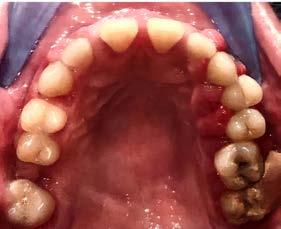

Caso clínico: paciente femenino de 19 años, patrón dolicofacial, perfil convexo, clase II esqueletal debido a una retrusión mandibular, mordida abierta anterior esqueletal, clase II molar, clase canina no establecida por mordida abierta, apiñamiento severo superior e inferior y deglución atípica.

Resultados: obtención de una clase canina I y clase molar II funcional, se corrigieron las sobremordidas horizontal y vertical, y se logró la coincidencia de líneas medias facial y dental. El manejo de la mordida abierta anterior se llevó a cabo por medio de la corrección del hábito de deglución atípica con la ayuda de spikes de resina, elásticos intermaxilares y arcos utility, y se obtuvieron buenos resultados estéticos, dentales y funcionales.